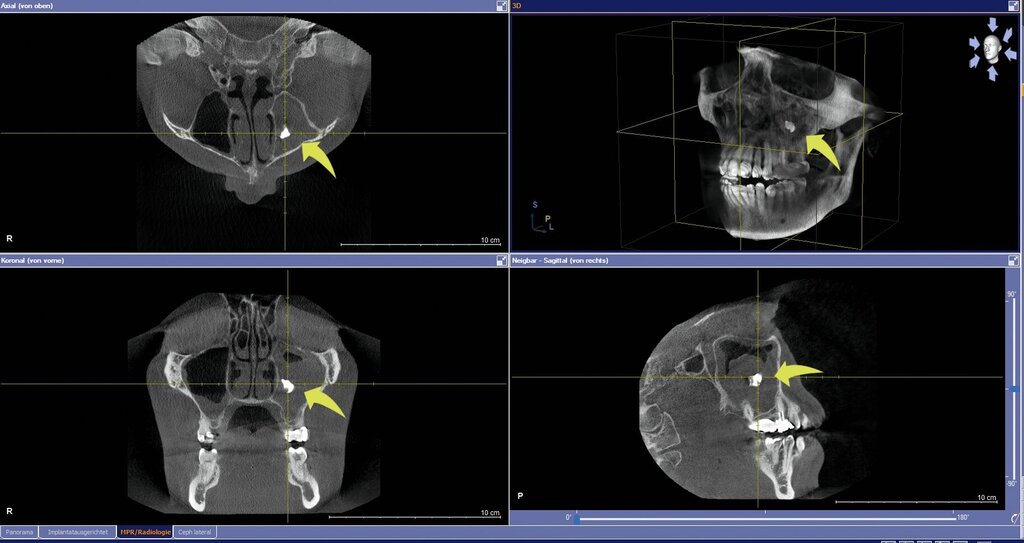

Zur weiteren Abklärung erfolgte eine digitale Volumentomografie (DVT), die eine subtotale Verschattung der linken Kieferhöhle sowie einen stark röntgendichten, metallisch anmutenden Fremdkörper von etwa 7 mm Größe zeigte. Weiter imponierte ein deutlicher vertikaler und horizontaler Knochenverlust im Bereich der ehemaligen Extraktionsalveole (Abbildung 2). Eine klinisch manifeste Mund-Antrum-Verbindung konnte jedoch nicht festgestellt werden.

Die Panoramaschichtaufnahme im Rahmen der zahnärztlichen Diagnostik kann bereits deutlich hyperdense Fremdkörper im Bereich des Sinus maxillaris zeigen. Die Lage des Aspergilloms selbst wird mittels dreidimensionaler Bildgebung näher bestimmt. Die dreidimensionale Bildgebung mittels digitaler Volumentomografie oder Computertomografie ist die Diagnostik der Wahl, um den Verdacht zu bestätigen. Typischerweise findet sich eine einseitige, subtotale Verschattung, assoziiert mit einem hyperdensen Fokus, gegebenenfalls eine Sklerosierung der begrenzenden Kieferhöhlenwand [Grosjean et Weber, 2007], Kalzifikationen [Ciapuccini et al., 2017] oder metalldichte Verschattungen [Torul et al., 2018].

Eine Sklerosierung der angrenzenden Kieferhöhlenwand deutet auf das lange Fortbestehen einer chronischen Entzündung hin [Giotakis et al., 2020]. Knöcherne Arrosionen verweisen auf ihre Infiltration [Han et al., 2023]. Die Magnetresonanztomografie kann ebenfalls Hinweise auf ein Aspergillom liefern, da das dicht zusammengelagerte Mycel selbst aus nahezu flüssigkeitsfreiem Material besteht und sich in der T2-Gewichtung gut von der entzündlich verdickten Kieferhöhlenschleimhaut abgrenzen lässt [Winkler et al., 2001].